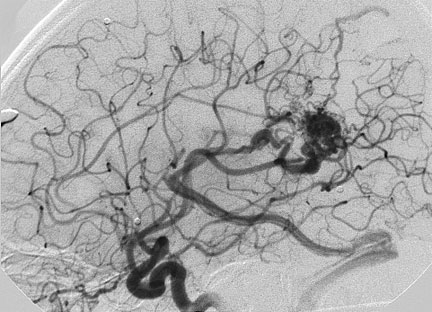

CASO 2 : Embolización combinada con Radiocirugía. Paciente con crisis convulsivas y trastorno del lenguaje. La angiografía demuestra voluminosa MAV localizada en plena área del lenguaje.

Angiografía 7 años después de la embolización mostrando reducción importante y definitiva del volumen de la MAV, convirtiéndola en blanco óptimo para radiocirugía

Al cabo de 18 meses de la radiocirugía la MAV está curada sin efectos adversos ni secuelas. El paciente continuó su trabajo e incluso estudios de post grado.